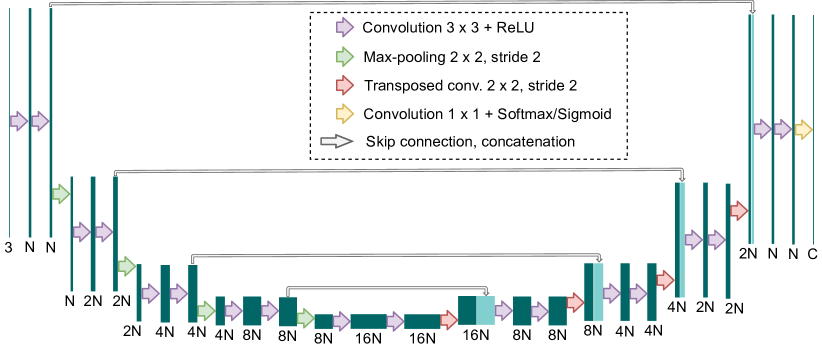

In Figure 5, a scheme of the U-Net architecture is shown. As can be seen in the figure, the network is composed of two main paths almost symmetrical: a contracting path (encoder), and an expansive path (decoder). This encoder-decoder shape is complemented with skip connections via concatenation between both paths.

The contracting path, or encoder, consists of 4 downsampling blocks. These blocks comprise two convolutions, each followed by a ReLU, and a max-pooling of stride 2. Thus, after each downsampling block, the spatial resolution is halved. Moreover, the number of feature maps is duplicated.

The expansive path, or decoder, is composed of 4 upsampling blocks and, as said, it is almost symmetrical to the encoder. Each upsampling block consists of two convolutions, each followed by a ReLU, and a transposed convolution. These transposed convolutions produce the opposite effect to the max-pooling operations, duplicating the spatial resolution. Also, the number of feature maps is reduced by half. The result of each transposed convolution is then concatenated with the feature maps of the same spatial resolution from the contracting path through a skip connection. In this way, the features from the contracting path are transferred to the expanding path at different resolution levels, leading to more detailed results in the network output.

In the final part of the network, two convolutions followed by a ReLU are applied to the result of the latter upsampling block, and then, a last convolution of is used to reduce the number of feature maps as desired (e.g. to a certain number of classes). In the MS approach, a sigmoid activation function is applied at the last convolutional layer, while in the traditional approach, the last layer is followed by a softmax layer.